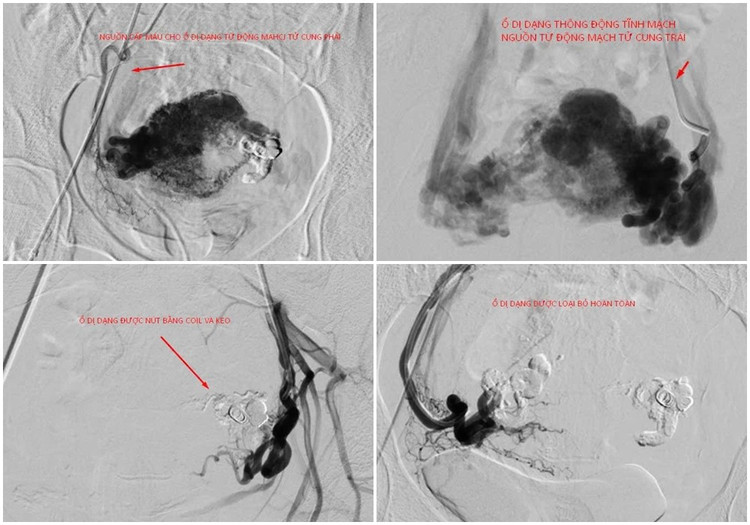

Qua hội chẩn các chuyên khoa, các bác sĩ chỉ định thực hiện can thiệp nút mạch tử cung chảy máu cấp cứu để vừa xử trí tình trạng chảy máu cấp tính, vừa bảo tồn tử cung cho người bệnh. Kíp thực hiện do BS.CKII Ngô Quang Chức, Trưởng khoa Chẩn đoán hình ảnh và BSCKI Đào Văn Đạt cùng các kỹ thuật viên.

Dưới hướng dẫn của hệ thống chụp mạch xóa nền 2 bình diện DSA, các bác sĩ luồn ống thông chuyên dụng đến vị trí ổ dị dạng và tiến hành nút mạch bằng keo sinh học và coil. Kiểm tra thấy các nhánh động mạch tử cung hai bên cấp máu cho ổ thông động tĩnh mạch đã được nút tắc hoàn toàn và triệt để.

tu-cung-thong-1.jpg

Hình ảnh ổ thông động tĩnh mạch tử cung với nguồn cấp máu phức tạp được kíp can thiệp nút mạch loại bỏ hoàn toàn - Ảnh BVCC

BS.CKII Ngô Quang Chức cho biết: “Trường hợp bệnh nhân H. phát hiện ổ thông động tĩnh mạch có nhiều nguồn cấp máu phức tạp, nguy cơ lớn nhất là xuất huyết ồ ạt, thậm chí có thể gây sốc mất máu, đe dọa tính mạng.